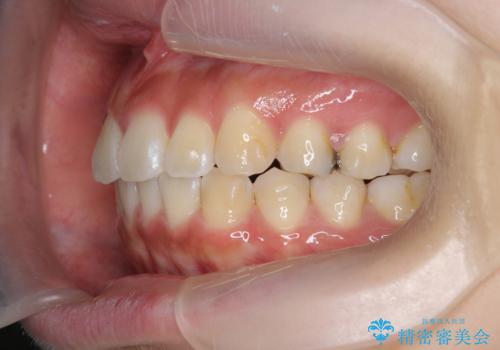

- 前歯の目立つねじれを矯正治療で治したい、と来院されました。

マウスピース矯正を始める前に、ねじれを取るのが短期間で済む部分ワイヤー小矯正を行うことで、全体的な治療期間を短くする治療計画を実行していきます。

前歯のねじれはマウスピース矯正の苦手な動きになり、治療期間が長くなる原因になりやすいです。